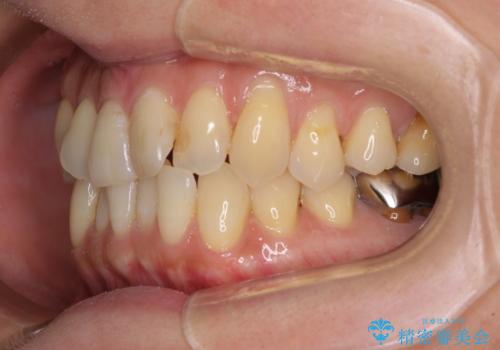

- 前歯のクロスバイトが気になり、インビザラインによる矯正治療を希望して来院された患者様です。

上顎側切歯(上の真ん中から2番目の歯)が舌側転位している場合、インビザラインでは仕上げきれないことが多く、更には無理して動かそうとすると歯髄壊死を起こすリスクが高いと言われています。

インビザラインで歯列を移動する前に、上顎前歯をワイヤー矯正で整え、その後上下歯列をインビザラインにて矯正治療を行うこととしました。

舌側転位している側切歯特有の、切縁の位置が不揃いであったり、根元が内側に引っ込んだ状態であったりという、インビザライン独特の仕上がりになることなく、きれいに整った歯列とすることができました。